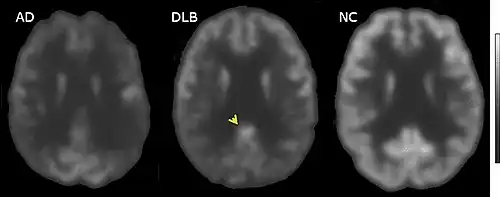

Direct laboratory-measurable biomarkers for DLB diagnosis are not known, but several indirect methods can lend further evidence for diagnosis.[24] The indicative diagnostic biomarkers are: reduced dopamine transporter uptake in the basal ganglia shown on PET or SPECT imaging; low uptake of 123iodine-metaiodobenzylguanidine (123I-MIBG) shown on myocardial scintigraphy; and loss of atonia during REM sleep evidenced on polysomnography. Supportive diagnostic biomarkers (from PET, SPECT, CT, or MRI brain imaging studies or EEG monitoring[121]) are: lack of damage to medial temporal lobe (damage is more likely in Alzheimer's disease[113]); reduced occipital activity; and prominent slow-wave activity on EEG.[24]

If DLB is suspected when parkinsonism and dementia are the only presenting features, PET or SPECT imaging may show reduced dopamine transporter activity. A DLB diagnosis may be warranted if other conditions with reduced dopamine transporter uptake can be ruled out.[24]

Since 2001, 123iodine-metaiodobenzylguanidine (123I-MIBG) myocardial scintigraphy has been used diagnostically in East Asia (principally Japan),[39][131][132] but not in the US.[113] MIBG is taken up by sympathetic nerve endings, such as those that innervate the heart, and is labeled for scintigraphy with radioactive 123iodine.[132] Autonomic dysfunction resulting from damage to nerves in the heart in patients with DLB is associated with lower cardiac uptake of 123I-MIBG.[132]

PET or SPECT imaging can be used to detect reduced dopamine transporter uptake and distinguish AD from DLB.[56][144] Severe atrophy of the hippocampus is more typical of AD than DLB.[145] Before dementia develops (during the mild cognitive impairment phase), MRI scans show normal hippocampal volume. After dementia develops, MRI shows more atrophy among individuals with AD, and a slower reduction in volume over time among people with DLB than those with AD.[32] Compared to people with AD, FDG-PET brain scans in people with DLB often show a cingulate island sign.[32]

In East Asia, particularly Japan,123I-MIBG is used in the differential diagnosis of DLB and AD, because reduced labeling of cardiac nerves is seen only in Lewy body disorders.[111][132] Other indicative and supportive biomarkers are useful in distinguishing DLB and AD (preservation of medial temporal lobe structures, reduced occipital activity, and slow-wave EEG activity).[24]